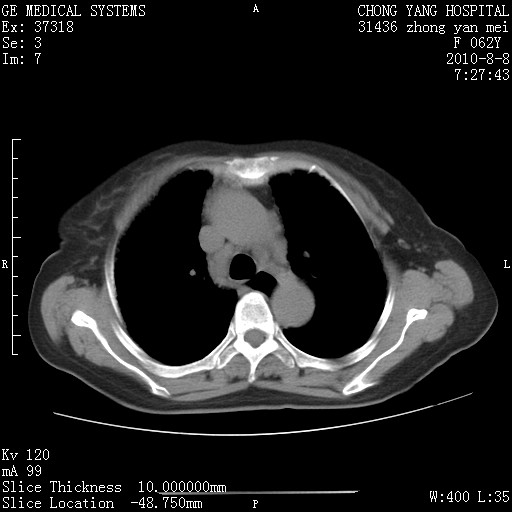

1.肺间质纤维化.

2.纵隔淋巴结肿大。

3.迷走右锁骨下动脉。

两肺间质改变,纵隔淋巴结肿大,需要考虑结节病的可能。